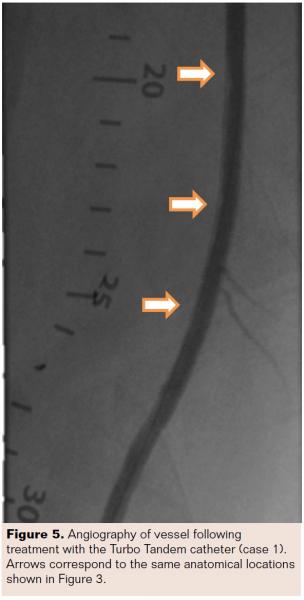

Following the 8 passes (Figure 5), the TT was removed and the angioplasty balloon was inserted to the lesion site. One inflation with the balloon at 18 atm for 120 seconds reduced the diameter stenosis to 24% (Figure 6). Long, slow inflations are recommended to prevent vessel dissections and tissue recoil. The procedure was successful with no adverse device-related events. This patient was followed for 12 months without the need for revascularization.